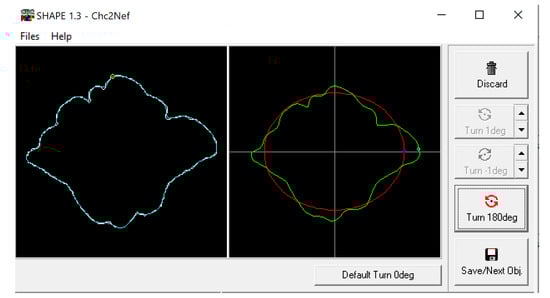

2.1. Morphological Analysis

3.1. Shape Variation Analysis